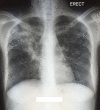

Drug-resistant tuberculosis (DR-TB) continues to pose a threat to the global eradication of TB. Regimens for extensively drug-resistant (XDR) TB are lengthy and poorly tolerated, often with unsuccessful outcomes. The TB Alliance Nix-TB trial investigated the safety and efficacy of a 26-week regimen of bedaquiline, pretomanid and linezolid (BPaL) in participants with XDR-TB, multidrug-resistant (MDR) TB treatment failure or intolerance. In this trial 9 out of 10 participants were cured. We describe a trial participant with XDR-TB who presented with new-onset seizures soon after BPaL treatment completion. Imaging showed a right temporal ring-enhancing lesion, and a sterile tuberculous granuloma was confirmed after a diagnostic, excisional biopsy. Learning points include management of a participant with a tuberculoma after BPaL completion, efficacy of new medications for central nervous system (CNS) TB and a review of their CNS penetration. This is the first case of pretomanid use in CNS TB.